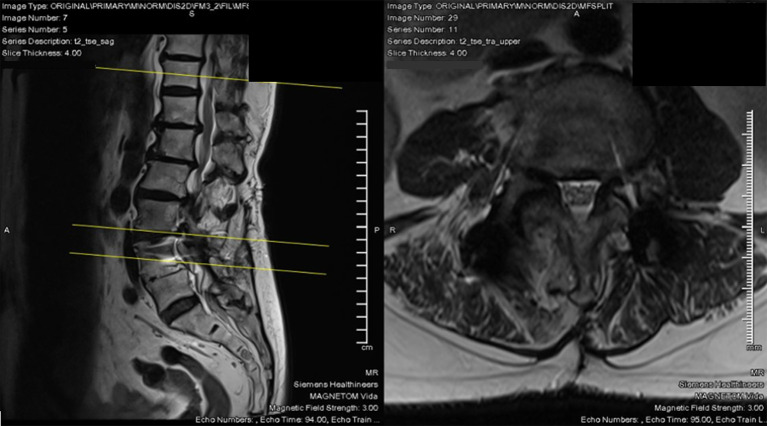

Case description: A 69-year-old woman with a prior L4/L5 TLIF presented to the clinic with a new onset of right lower limb radiculopathy along the L3 dermatome, as well as numbness in the L2 distribution. Magnetic resonance imaging (MRI) studies revealed adjacent segment degeneration in L2/L3 and L3/L4, with disc-osteophyte complexes impinging onto the exiting L2 and L3 nerve roots, respectively. We opted for a right L2/L3 and L3/L4 unilateral endoscopic biportal transforaminal decompression. The surgery was successful, with the patient being discharged from the hospital on postoperative day 1 with minimal pain. Within 2 weeks, the patient described significant improvement in both back pain and radiculopathy, and the numbness had completely resolved. Oswestry Disability Index was used to objectively quantify outcomes and saw an improvement from 15 to 0. Notably, there were no complications.